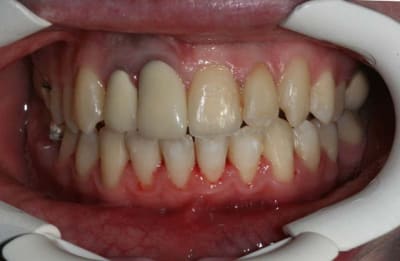

Voici le cas il y a 8 jours, c.a.d. 1 an et 1 mois après les photos de son dernier rendez vous

entre temps, elle est allée se faire faire des provisoires sur 12/11 par un confrère plus prés de son domicile

voici le résultat de l’absence de contention, qui aurait été (a mon avis) une erreur compte tenu que le cas n’était pas terminé

c’est mal foutu, c’est déglingué mais je n’ai aucune malposition Inc. Inf.

c.a.d. : AUCUNE RECIDIVE D’ENCOMBREMENT AVEC ROTATIONS

les dents ne sont pas alignées, mais j’ai mon espace globale, je peux poursuivre ce traitement avec sérénité

elle n’est pas défigurée,

elle n’a pas de migraines

pas d’acouphènes

pas de DAM.

etc ...